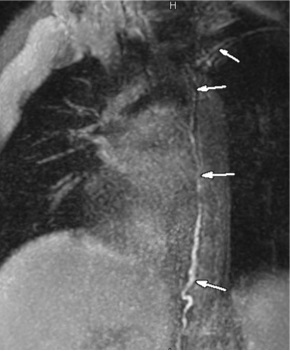

MR lymphangiography 女性 20岁 4个月前,乳糜胸腹水, 引流量150ml/日,三油甘脂水平2812mg/dL 逆行性胸导管入路 Retrograde TD access

MR lymphangiography

女性 20岁 4个月前,乳糜胸腹水, 引流量150ml/日,三油甘脂水平2812mg/dL

逆行性胸导管入路 Retrograde TD access